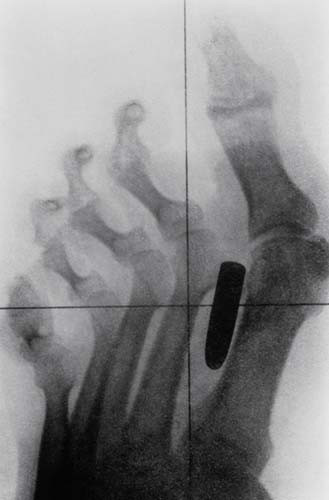

Tarihten bir röntgen filmi. Bir askerin ayak parmaklarının arasına saplanmış bir kurşun.

Bu röntgenler gerçek! - Resim: 4